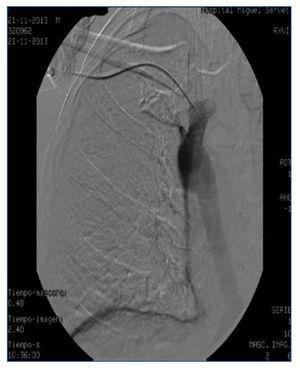

Figura 2.

Presentamos el caso de una paciente en hemodiálisis, que había agotado todas las posibilidades de realización de FAVI y que se dializaba a través de catéter yugular tunelizado colocado en yugular interna derecha. Anteriormente había sido portadora de varios catéteres en vena yugular derecha e izquierda y en ambas femorales, habiendo desarrollado trombosis de estas como complicación asociada. Por malfuncionamiento del catéter yugular derecho se realiza cavografía, que muestra trombosis oclusiva de toda la vena cava superior con gran hipertrofia de la vena ácigos (figura 1). Se intenta abordaje por vía yugular derecha, que es imposible debido a su trombosis, por lo que se realiza abordaje subclavio derecho y se consigue implantar el catéter dejando el extremo distal próximo al cayado de la ácigos (figura 2). La paciente se dializó a través de este catéter sin incidencias, con flujos de 300-350 ml/min consiguiéndose un KTV medio de 1,64 durante 4 meses, momento en que fue sometida a un trasplante renal de donante cadáver. La colocación de catéteres en la vena ácigos está descrita en numerosas ocasiones como complicación del procedimiento en el abordaje de accesos vasculares subclavios o yugulares. Sin embargo, con nuestro caso mostramos que la vena ácigos puede ser una alternativa válida como acceso venoso central funcionante, con buenos flujos y buena calidad de diálisis en pacientes con trombosis en los territorios venosos habituales.